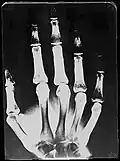

Vorlage: Röntgenaufnahme rechter Hand;

farbige Äquidensitenschar